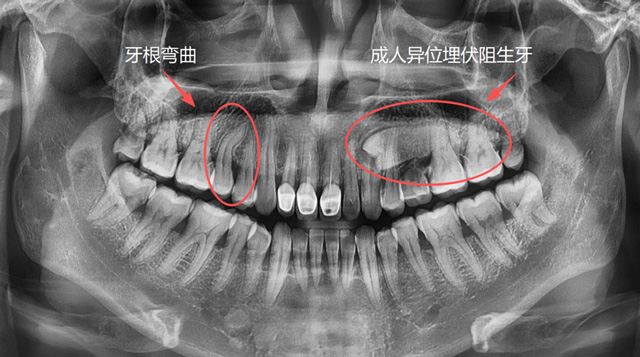

想要让一颗牙脱位,直的牙根是比较好操作的,弯的牙根因为有一定的弧度,需要顺着这个弧度来解除阻力。如果反着用力,可能会造成牙根折断,取断根需要去骨,就会损失一些牙槽骨的骨量。

成人牙根弯曲、异位埋伏阻生牙

总的来说,医生会根据牙齿的解剖结构和位置等因素去判断阻力,去分析怎么把这个阻力解除,再采用相应的手术方案和工具来完成手术。